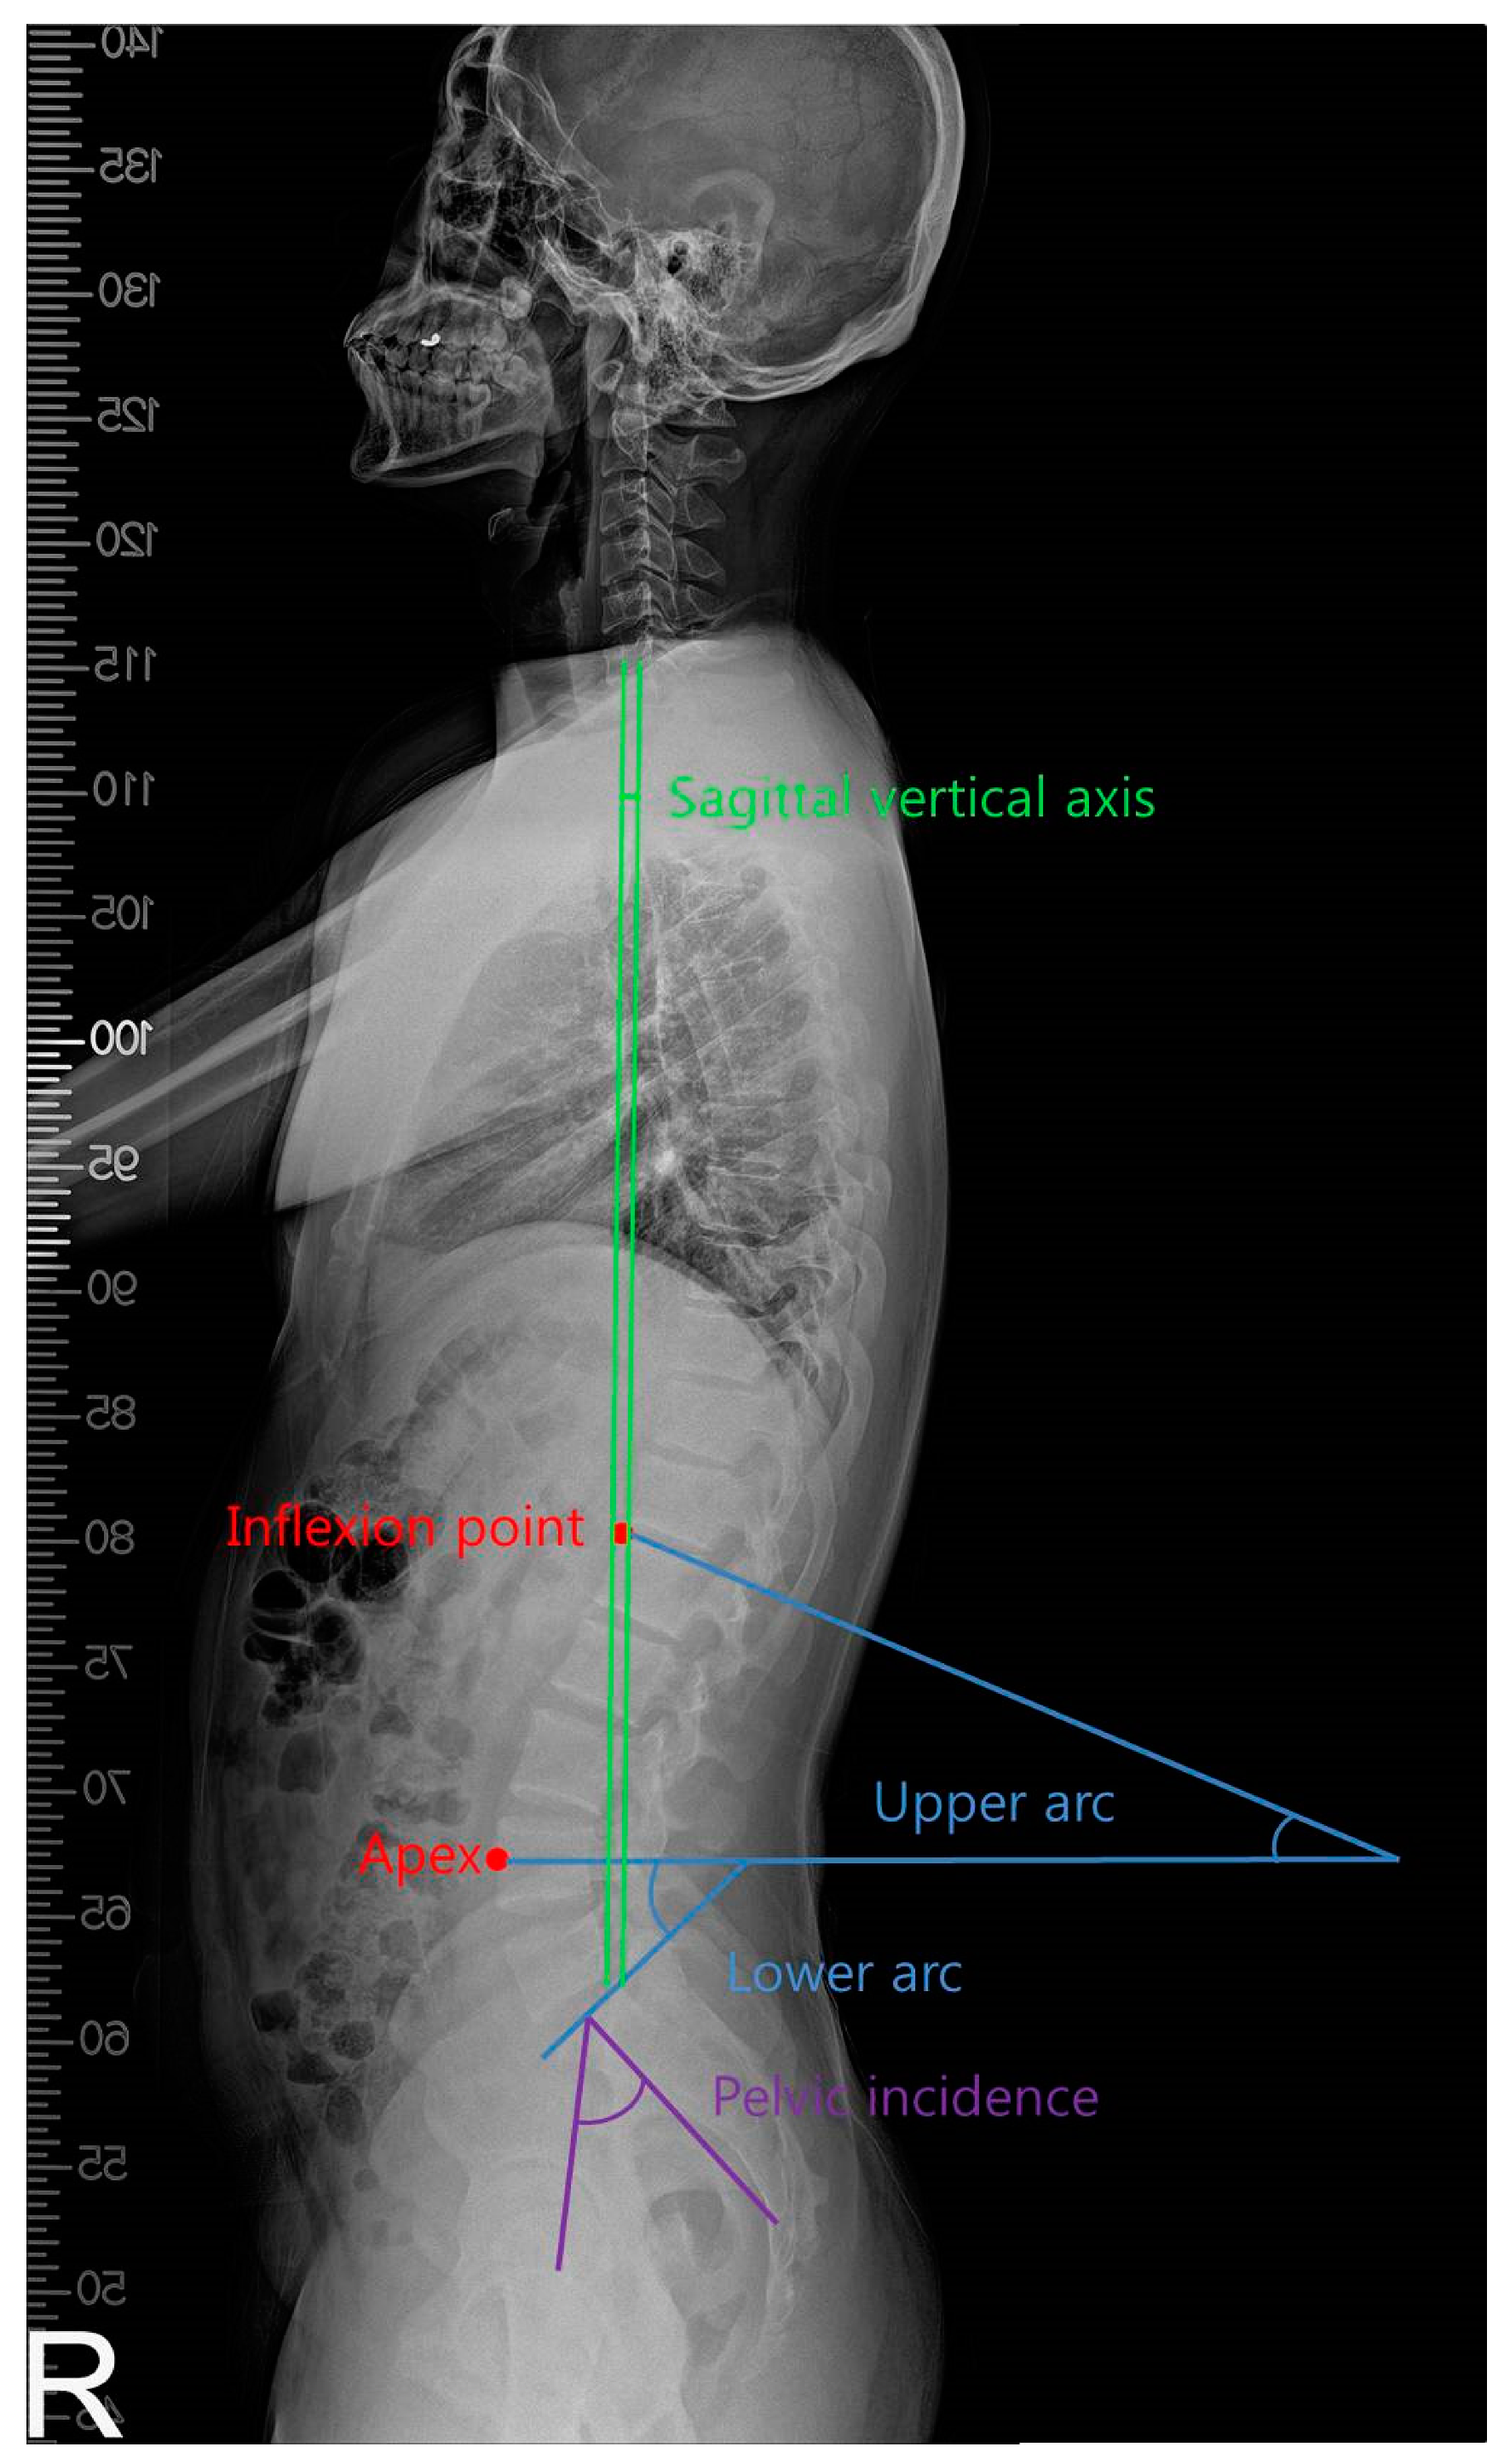

2.3. Measurement

| Whole arc (degree) | 49.0 ± 6.6 # | 44.0 ± 8.3 *,† | 47.6 ± 9.8 # | 5.583 | 0.008 |

| Upper arc (degree) | 9.3 ± 4.6 | 8.6 ± 3.4 | 8.5 ± 3.9 | 0.442 | 0.646 |

| Lower arc (degree) | 39.7 ± 3.2 # | 35.3 ± 5.8 *,† | 39.1 ± 7.8 # | 6.783 | 0.003 |

| SVA (mm) | 25.2 ± 16.8 # | 49.3 ± 16.1 *,† | 46.9 ± 11.2 # | 10.837 | 0.001 |